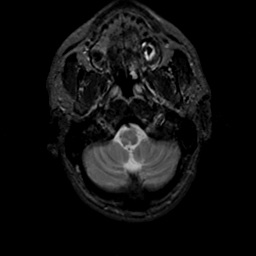

MR Study #18, July 21, 1991 -- Slice #5